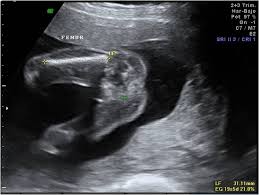

Mide la longitud del fémur el hueso del muslo y se expresa en milímetros. Por sunnyfunny Mié Oct 08 2008 859 pm. LF en español es longitud del fémur expresada en milímetros.

Se usa para conocer tanto el peso del bebé como su longitud especialmente en la última etapa del embarazo. Determinación de fetometría así como revisión cardiaca riñones vejiga abdomen columna extremidades y el SNC. CC en español corresponde al perímetro de la cabeza siempre en milímetros.

La cilindrada por ser una medida de volumen se expresa en centímetros cúbicos litros o pulgadas cúbicas. Por sunnyfunny Mié Oct 08 2008 859 pm. Determina la fecha de la última menstruación de la mamá. Se trata de un sistema por convenio para valorar la progresión del embarazo y se empieza a contabilizar desde 2 semanas antes de la concepción. Un bebé recién nacido habrá ganado la mitad de su peso total durante el último trimestre. Se consideró como biometría fetal estándar a la medición del diámetro biparietal DBP circunferencia cefálica CC longitud del fémur LF y circunferencia abdominal CA. Tengo 225 sem de embarazo. Si desea saber cuál es la longitud del feto sin esperar a la siguiente ecografía puede usar una calculadora en línea ingresando la longitud del fémur en el sistema de cálculo un parámetro que se indica en la última ecografía realizada. COLUMNA CORAZON DE 4 CAMARAS.

Ultrasonido de diagnóstico es una técnica de diagnóstico no invasiva que se utiliza para producir imágenes dentro del cuerpo. Que significa cc en un ultrasonido. CRL Diámetro Biparietal Longitud del Fémur Circunferencia Abdominal Edad Gestacional etc. El perímetro abdominal del bebé expresado en milímetros. Aproximadamente la longitud del feto es 7 veces mayor que la del fémur. EPF en español estimación del peso del feto en gramos. Es la fecha estimada del parto.